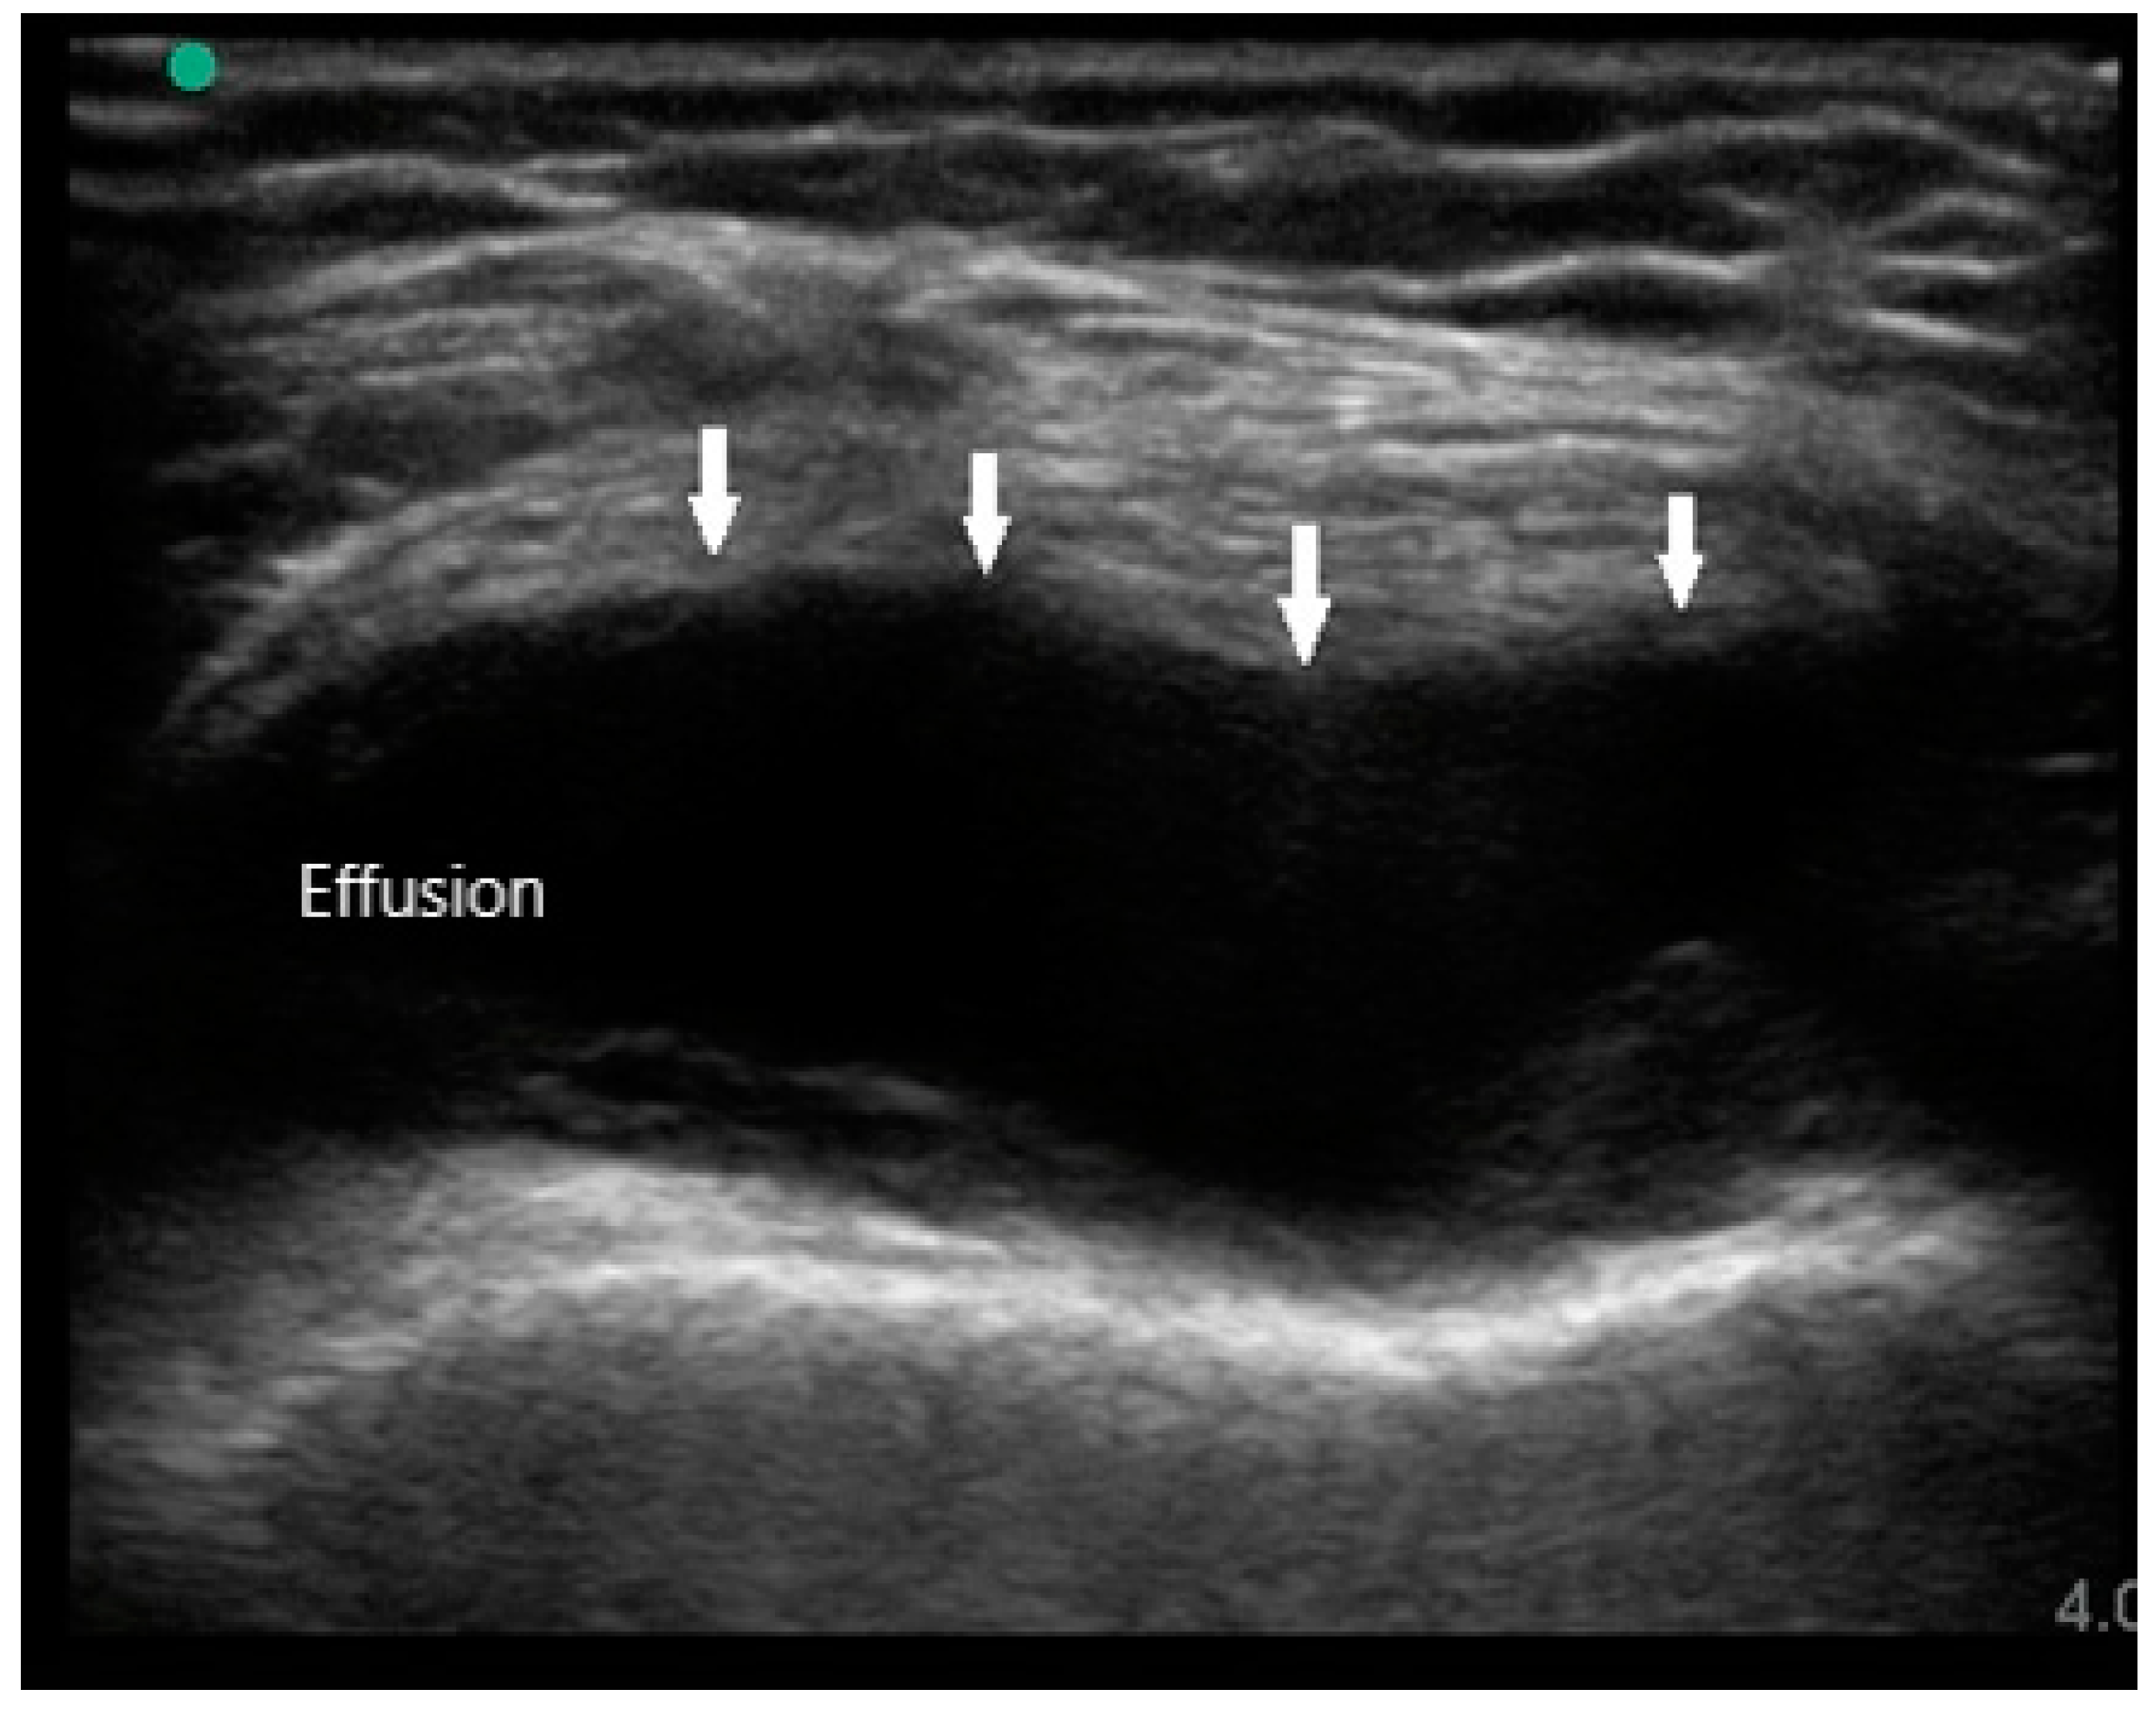

MSUS is primarily used to assist in diagnosis by identifying the presence of synovitis in symptomatic joints, especially if physical examination is difficult or equivocal. The sonographic features of RA are joint effusion, synovial hypertrophy, bone erosions, tenosynovitis, and hyperemia. Joint effusions appear as compressible hypoechoic or anechoic material in the joint space, often detected in the dependent recesses of the synovium. For large joints such as knees, effusions are most easily seen in the suprapatellar fossa in either long or short axis (Figure 1). In small joints such as PIPs, effusions can be detected over the joint on the palmar aspect deep to the flexor tendon. While the presence of joint effusion does not prove the presence of inflammatory arthritis, it does supplement the physical exam and indicate the potential need for arthrocentesis and synovial fluid analysis.

Figure 1. Knee effusion (arrows) in suprapatellar short axis view.